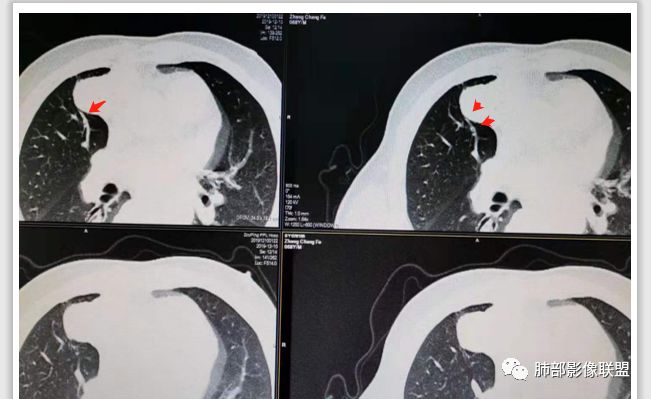

20例畸胎瘤钙化特点

有脂肪密度畸胎瘤

有脂肪,有钙化,钙化为条状,不是块状,偏心

多在前纵隔,可跨纵隔。就是从前跨到中的比较多

随机翻阅以上20个病例,都是畸胎瘤伴钙化的,发现只有2例钙化是团块状,且都是偏心的。其余18例钙化都是颗粒状、条状和包膜弧形钙化。有9例是多发钙化,且比较散,不聚集。总之,比较少会出现单发中心性的团块钙化。20例均没有,虽然样本少,但是均符合王兆宇老师说的规律。

第一种是弧形钙化,是囊性畸胎瘤的弧形钙化。

第二种条状钙化可能是血管钙化,脉管钙化。

第三种团块状或一颗颗的可能是牙齿,一般都不会太大,而且比较散在。

胸腺瘤钙化

大部分钙化还是包膜钙化和条状,结节状钙化,团块状钙化也比较少。位置中央,周围都可以。